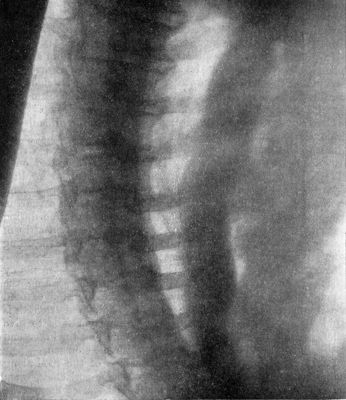

207.Compression Fracture of Bodies of Third and Fourth Lumbar Vertebræ426

208.Fracture-Dislocation of Ninth Thoracic Vertebra428

209.Fracture of Odontoid Process of Axis Vertebra429